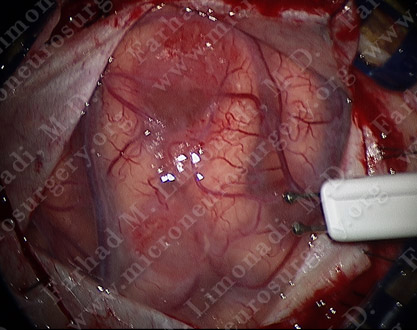

Motor cortex stimulation using Ojeman stimulator.